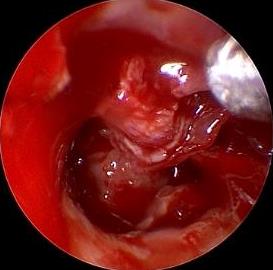

• 耳内镜下耳屏软骨-软骨膜鼓膜修补术后的短期疗效观察

摘要:目的 探讨耳内镜下耳屏软骨-软骨膜鼓膜修补术后的短期疗效。方法 回顾性分析2019年9月-2022年8月该院收治的78例鼓膜穿孔患者的临床资料,患者均采用耳内镜下鼓膜修补术。术后随访3个月,观察鼓膜形态和穿孔愈合情况,记录内镜图像、干耳时间、术前术后听力及耳鸣情况,以及外耳道狭窄等并发症的发生率。结果 术后3个月,鼓膜穿孔愈合率为97.44%(76/78),愈合良好,平均气导听阈较术前明显改善,气骨导间距较术前明显缩小,耳鸣较术前明显改善,差异均有统计学意义(P<0.05)。干耳时间为(4.21±1.12)周。术后出现肉芽5例,再穿孔2例,真菌感染2例,术腔感染、耳屏感染、外耳道狭窄和切口瘢痕各1例,所有患者术后均未发生面神经麻痹和感音神经性聋等严重并发症。结论 耳内镜下耳屏软骨-软骨膜鼓膜修补术是一种安全、有效的手术方法。根据术后愈合规律、内镜下鼓膜和外耳道形态特征,可为鼓膜修补术后正常中耳转归和并发症的诊疗,提供临床参考。